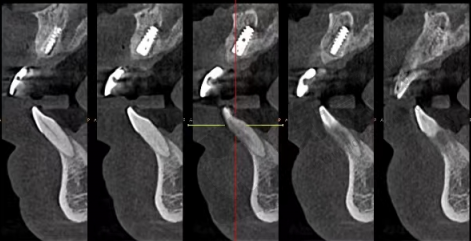

技术优势:2009 年掌握上颌窦开窗植骨种牙术和下齿槽神经避让种牙术,实现即拔即种,为前牙美学种植提供坚实技术支持,减少手术创伤和风险。

机构背景与优势:南宁岭南牙科是南宁当地老牌连锁机构,经卫健委审批成立的正规私立牙科,医疗资质信息可网上查询。它还是区、市医疗保险定点单位,目前拥有五家门店,诊疗项目丰富。在种植牙领域,2009 年就掌握了上颌窦开窗植骨种牙术和下齿槽神经避让种牙术,实现即拔即种,前牙美学种植项目结合这些精良技术,为患者提供优质服务。

潘蛟南医生:岭南牙科院长,毕业于广西医 科 大学,种植、正畸专科医生。2009 年攻克种植牙技术上颌窦开窗植骨种牙术,擅长即刻种植即刻修复即刻负重种植牙等多种技术。进行前牙美学种植时,能根据患者具体情况制定个性化方案,确保成效美观实用。